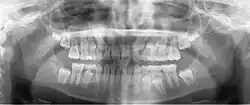

Минимально смещённый перелом правой нижней челюсти. Стрелка отмечает перелом, корневой канал на центральном резце, зубы слева от перелома не соприкасаются